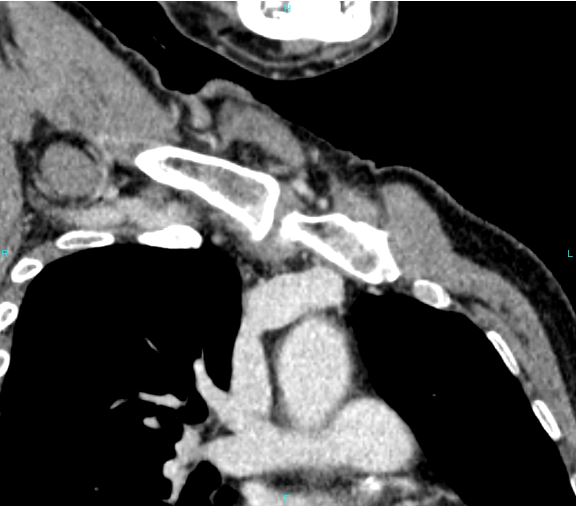

Image of CT venogram shows obstruction of the major vein in the chest